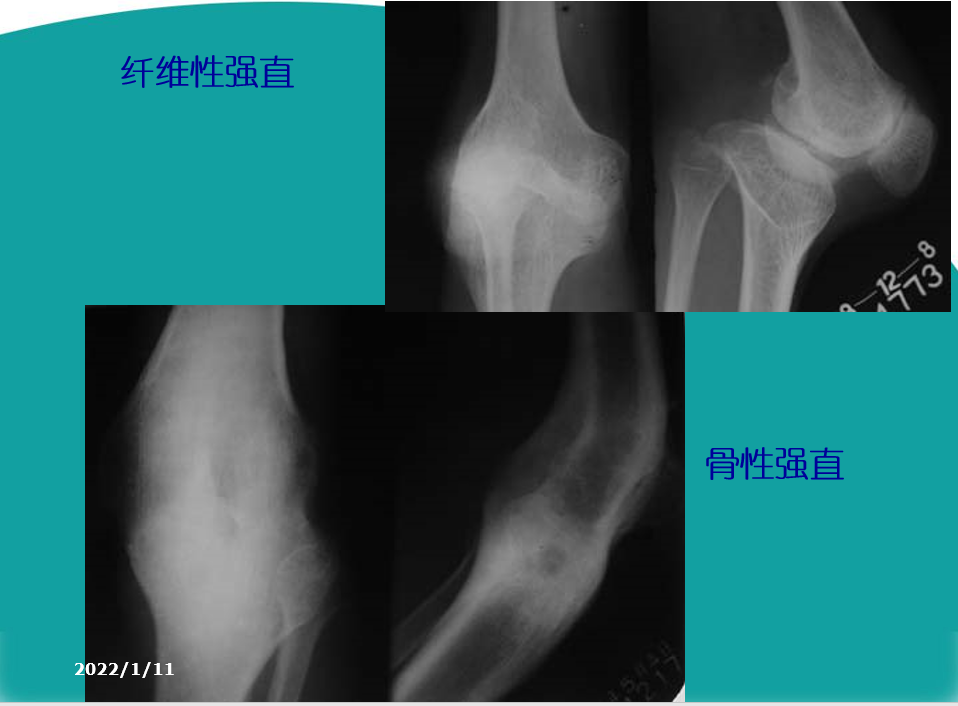

2.肿胀:部分患者关节肿胀,并反复发作。3.畸形:膝关节可出现内翻或外翻畸形,关节骨缘增大。有些患者不能完全伸直膝关节,严重者则膝关节呈屈曲挛缩畸形。4.功能障碍:运动节律异常:打软腿、弹响声、绞锁症。运动能力减弱:关节僵硬、不稳、屈伸受限、步行能力。

膝关节OA诊断标准1、近1个月内反复膝关节疼痛,活动功能减弱。2、X线片(站立或负重位)示关节间隙变窄、软骨下骨硬化、和(或)囊性变、关节缘骨赘形成。3、中老年患者(≥40岁)。 4、晨僵≤30 min 。5、活动时有骨摩擦音(感)。6、膝关节骨端肥大,局部呈不同程度肿胀 。   7、膝关节屈伸活动范围减少或受限。    8、膝关节畸形改变,以膝关节内翻畸形最为常见。